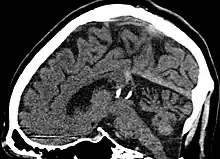

Calcified cyst of pineal gland in CT. Sagittal MPR. |